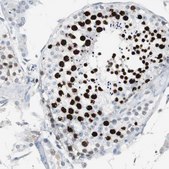

Anti-TOP2A antibody produced in rabbit

IHC

Anti-TOP2A antibody produced in rabbit, a Prestige Antibody, is developed and validated by the Human Protein Atlas (HPA) project . Each antibody is tested by immunohistochemistry against hundreds of normal and disease tissues. These images can be viewed on the Human Protein Atlas (HPA) site by clicking on the Image Gallery link. The antibodies are also tested using immunofluorescence and western blotting. To view these protocols and other useful information about Prestige Antibodies and the HPA, visit sigma.com/prestige.

• IHC tissue array of 44 normal human tissues and 20 of the most common cancer type tissues.